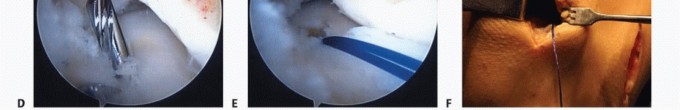

TECH FIG 2 • Lateral meniscal approach and tibial preparation. A,B. Creation of small trough between the anterior and posterior horn attachments. C. Rasping recipient site (visualized through medial portal). D,E. Tibial recipient site (dovetail trough) preparation. F. Posterolateral exposure. 2. ## Delivery and Fixation of Lateral Meniscus

1. ## Lateral Meniscus Approach and Tibial Preparation

A combined arthroscopic and lateral parapatellar arthrotomy approach is performed.

Placing the lateral portal just adjacent to the patellar tendon will optimize instrument access between the anterior and posterior horn insertion sites.

Perform an arthroscopic débridement and excoriation to the far peripheral meniscal rim or joint capsule with a shaver or meniscal rasp. Leaving 1 to 2 mm of intact peripheral meniscal rim is often beneficial, when possible.

A Beaver blade may be used to excise the anterior horn and any remnant of the body.

Initially, preserving the anterior and posterior horn attachment sites will guide the placement of the recipient trough.

Use an arthroscopic burr to create a small trough in line with the anterior and posterior horn attachments (guide for recipient site) (

TECH FIG 2A,B

).

Expose the proximal tibia through a small lateral parapatellar arthrotomy in line with the trough.

Commercially available instrumentation will facilitate creation of the tibial recipient site in line with the anterior and posterior horn attachments (

TECH FIG 2C-E

The trough is advanced to the posterior cortex but attempt to avoid penetration through the posterior cortex.

Perform posterolateral exposure to receive inside-out sutures (meniscus repair approach) (

TECH FIG 2F